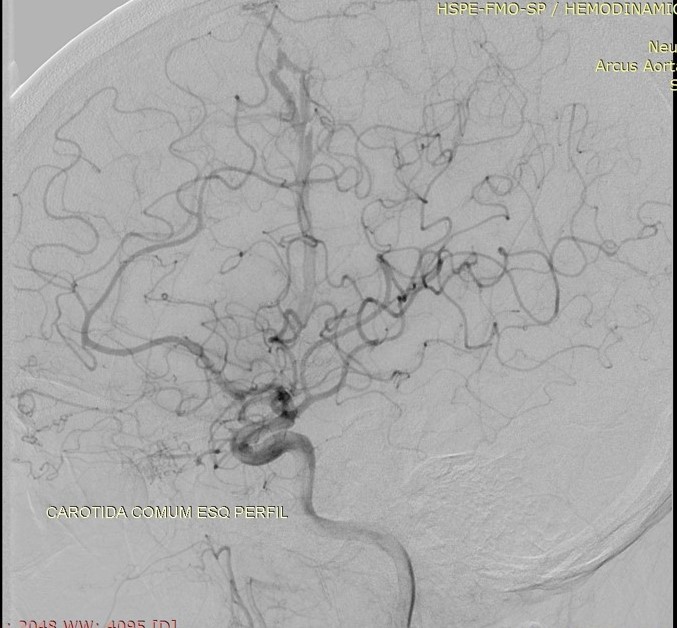

Discussão de tratamento de Fístula Arteriovenosa Dural grau I

Malformações artério venosas durais intracranianas - Discussão de caso fístula dural pós traumática grau I

Fístulas arteriovenosas durais (FAVDs) são lesões adquiridas, que consistem em uma ou mais conexões fistulosas no interior dos folhetos da dura-máter, envolvendo mais especificamente as paredes de um seio venoso dural ou as veias leptomeníngeas adjacentes.